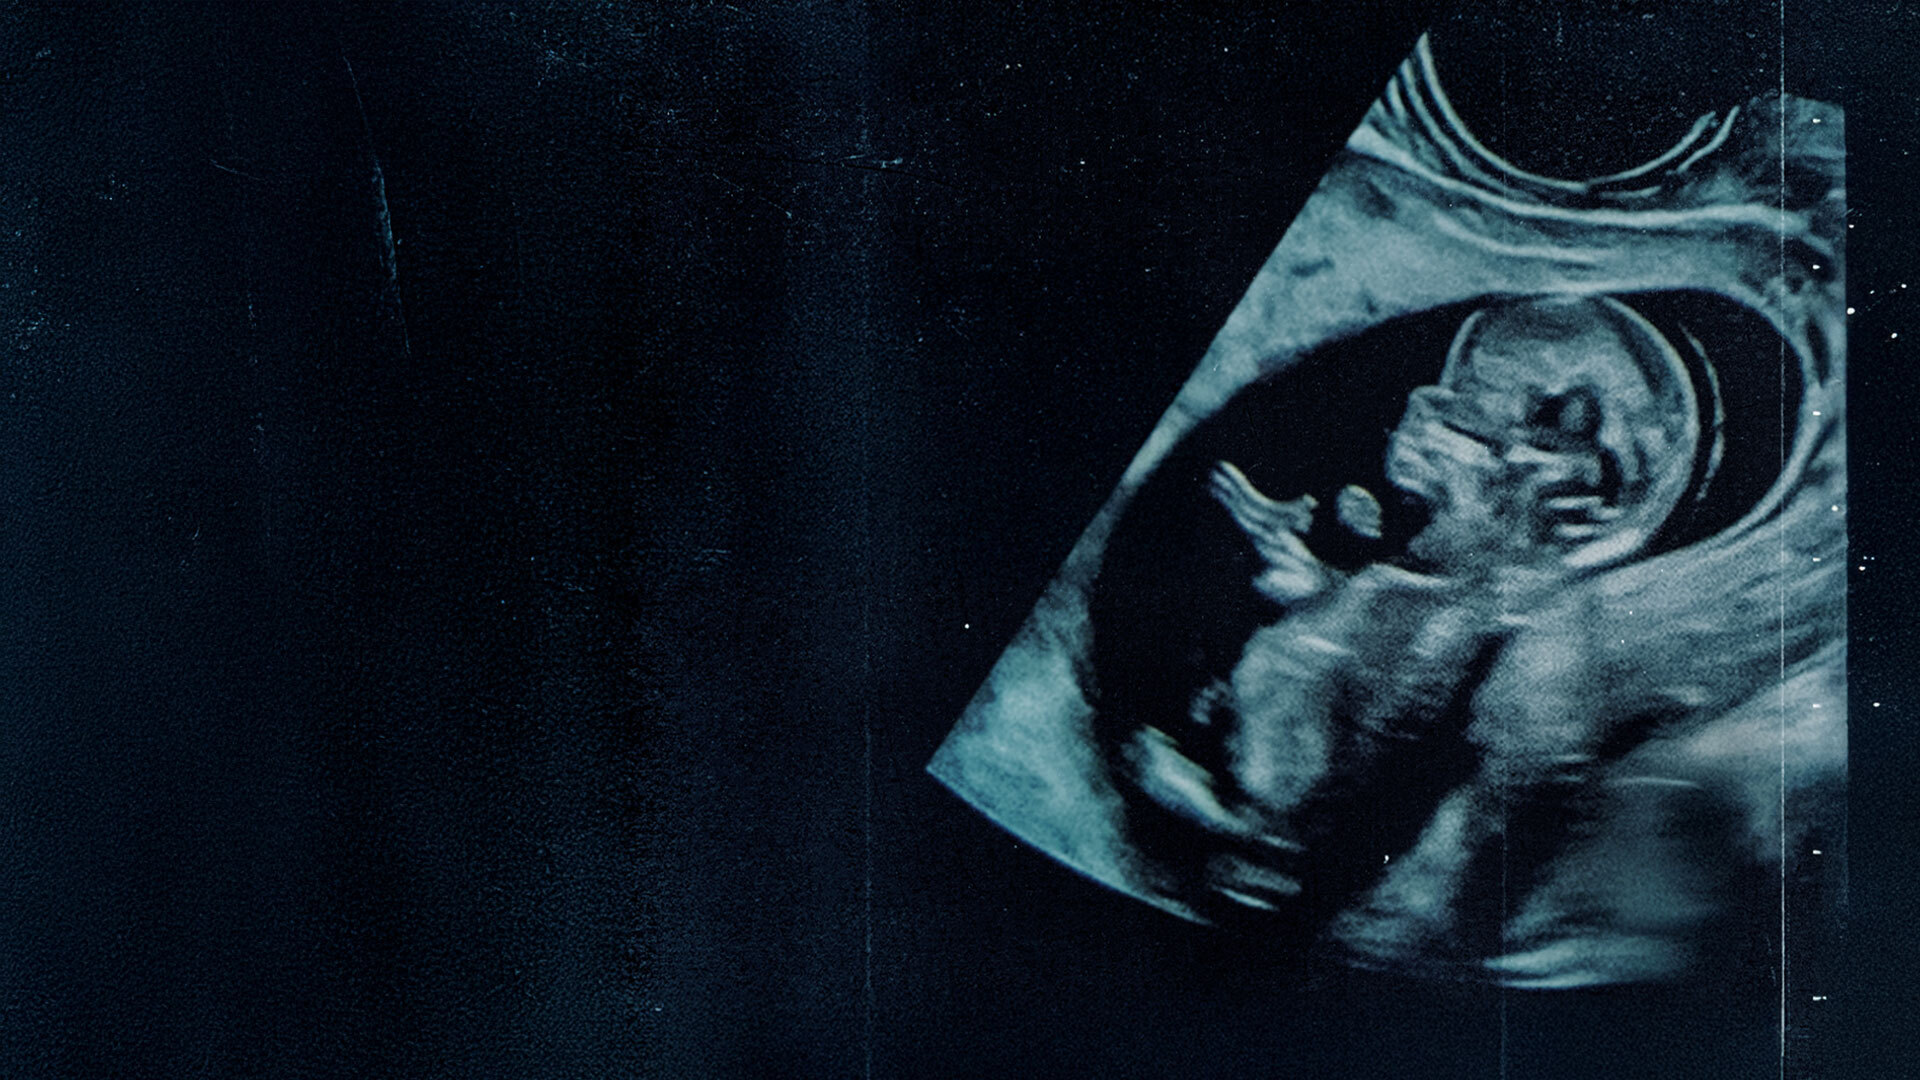

Um documentário que pode impactar a vida de milhões de seres humanos, os que já nasceram e os que ainda podem nascer — se receberem essa chance. É hora de entender por que ser Humano vale a pena e por que devemos apoiar as mães, que se sentem pressionadas e em dúvida, a fazerem a escolha mais desafiadora e fascinante: a escolha pela vida.